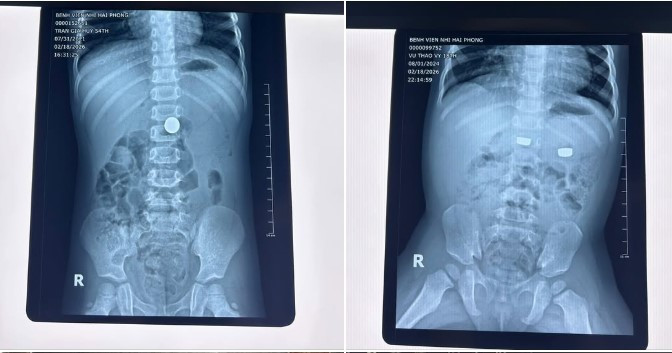

di-vat-2.jpg

Hình ảnh dị vật trong đường tiêu hóa và được lấy ra - Ảnh BVCC